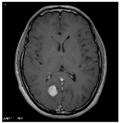

This work collects images from the Kaggle Brain MRI for Brain Tumor Detection dataset, which consists of 253 files with cancer and non-cancer brain images. The sample MRI is illustrated in Figure 2. The dataset has two folders: no tumor encoded as 0 and tumor as 1. The labeled data is more helpful in extracting the patterns from the MRI, which is used to predict the new images related output. The collected image consists of noise information that reduces the performance of brain tumor recognition accuracy. Therefore, image noise should be eliminated to improve the overall prediction efficiency.

Figure 2.

MRI samples Normal Brain MRI (Y1 to Y8) Benign tumor MRI (Y9 to Y15) Malignant tumor MRI (Y16 to Y21).